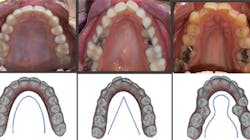

If we take the time to disclose the cause of disease, we can then focus on proper treatment modalities. The root cause of most crowded malocclusions is a result of three conditions: improper arch form, improper arch width, and improper buccolingual inclination (figure 1).

Figure 1: Examples of a proper U-shaped arch (left), an improper V-shaped arch (middle), an improper omega-shaped arch (right). Photos courtesy of Dr. Ben Miraglia.

As the transverse measurement decreases, so does the “home” for the tongue. In Figure 3, you notice the narrowing of the arch and the increased vault of the palate in direct proportion to the decreasing width of the transverse (McNamara) measurement.

Before: V-shaped arch. After: U-shaped arch.

Before: V-shaped arch. After: U-shaped arch; implant placed No. 14.

Before: V- and omega-shaped arch, crossbite. After: U-shaped arch, no IPR, no EXT, increased oral cavity volume.